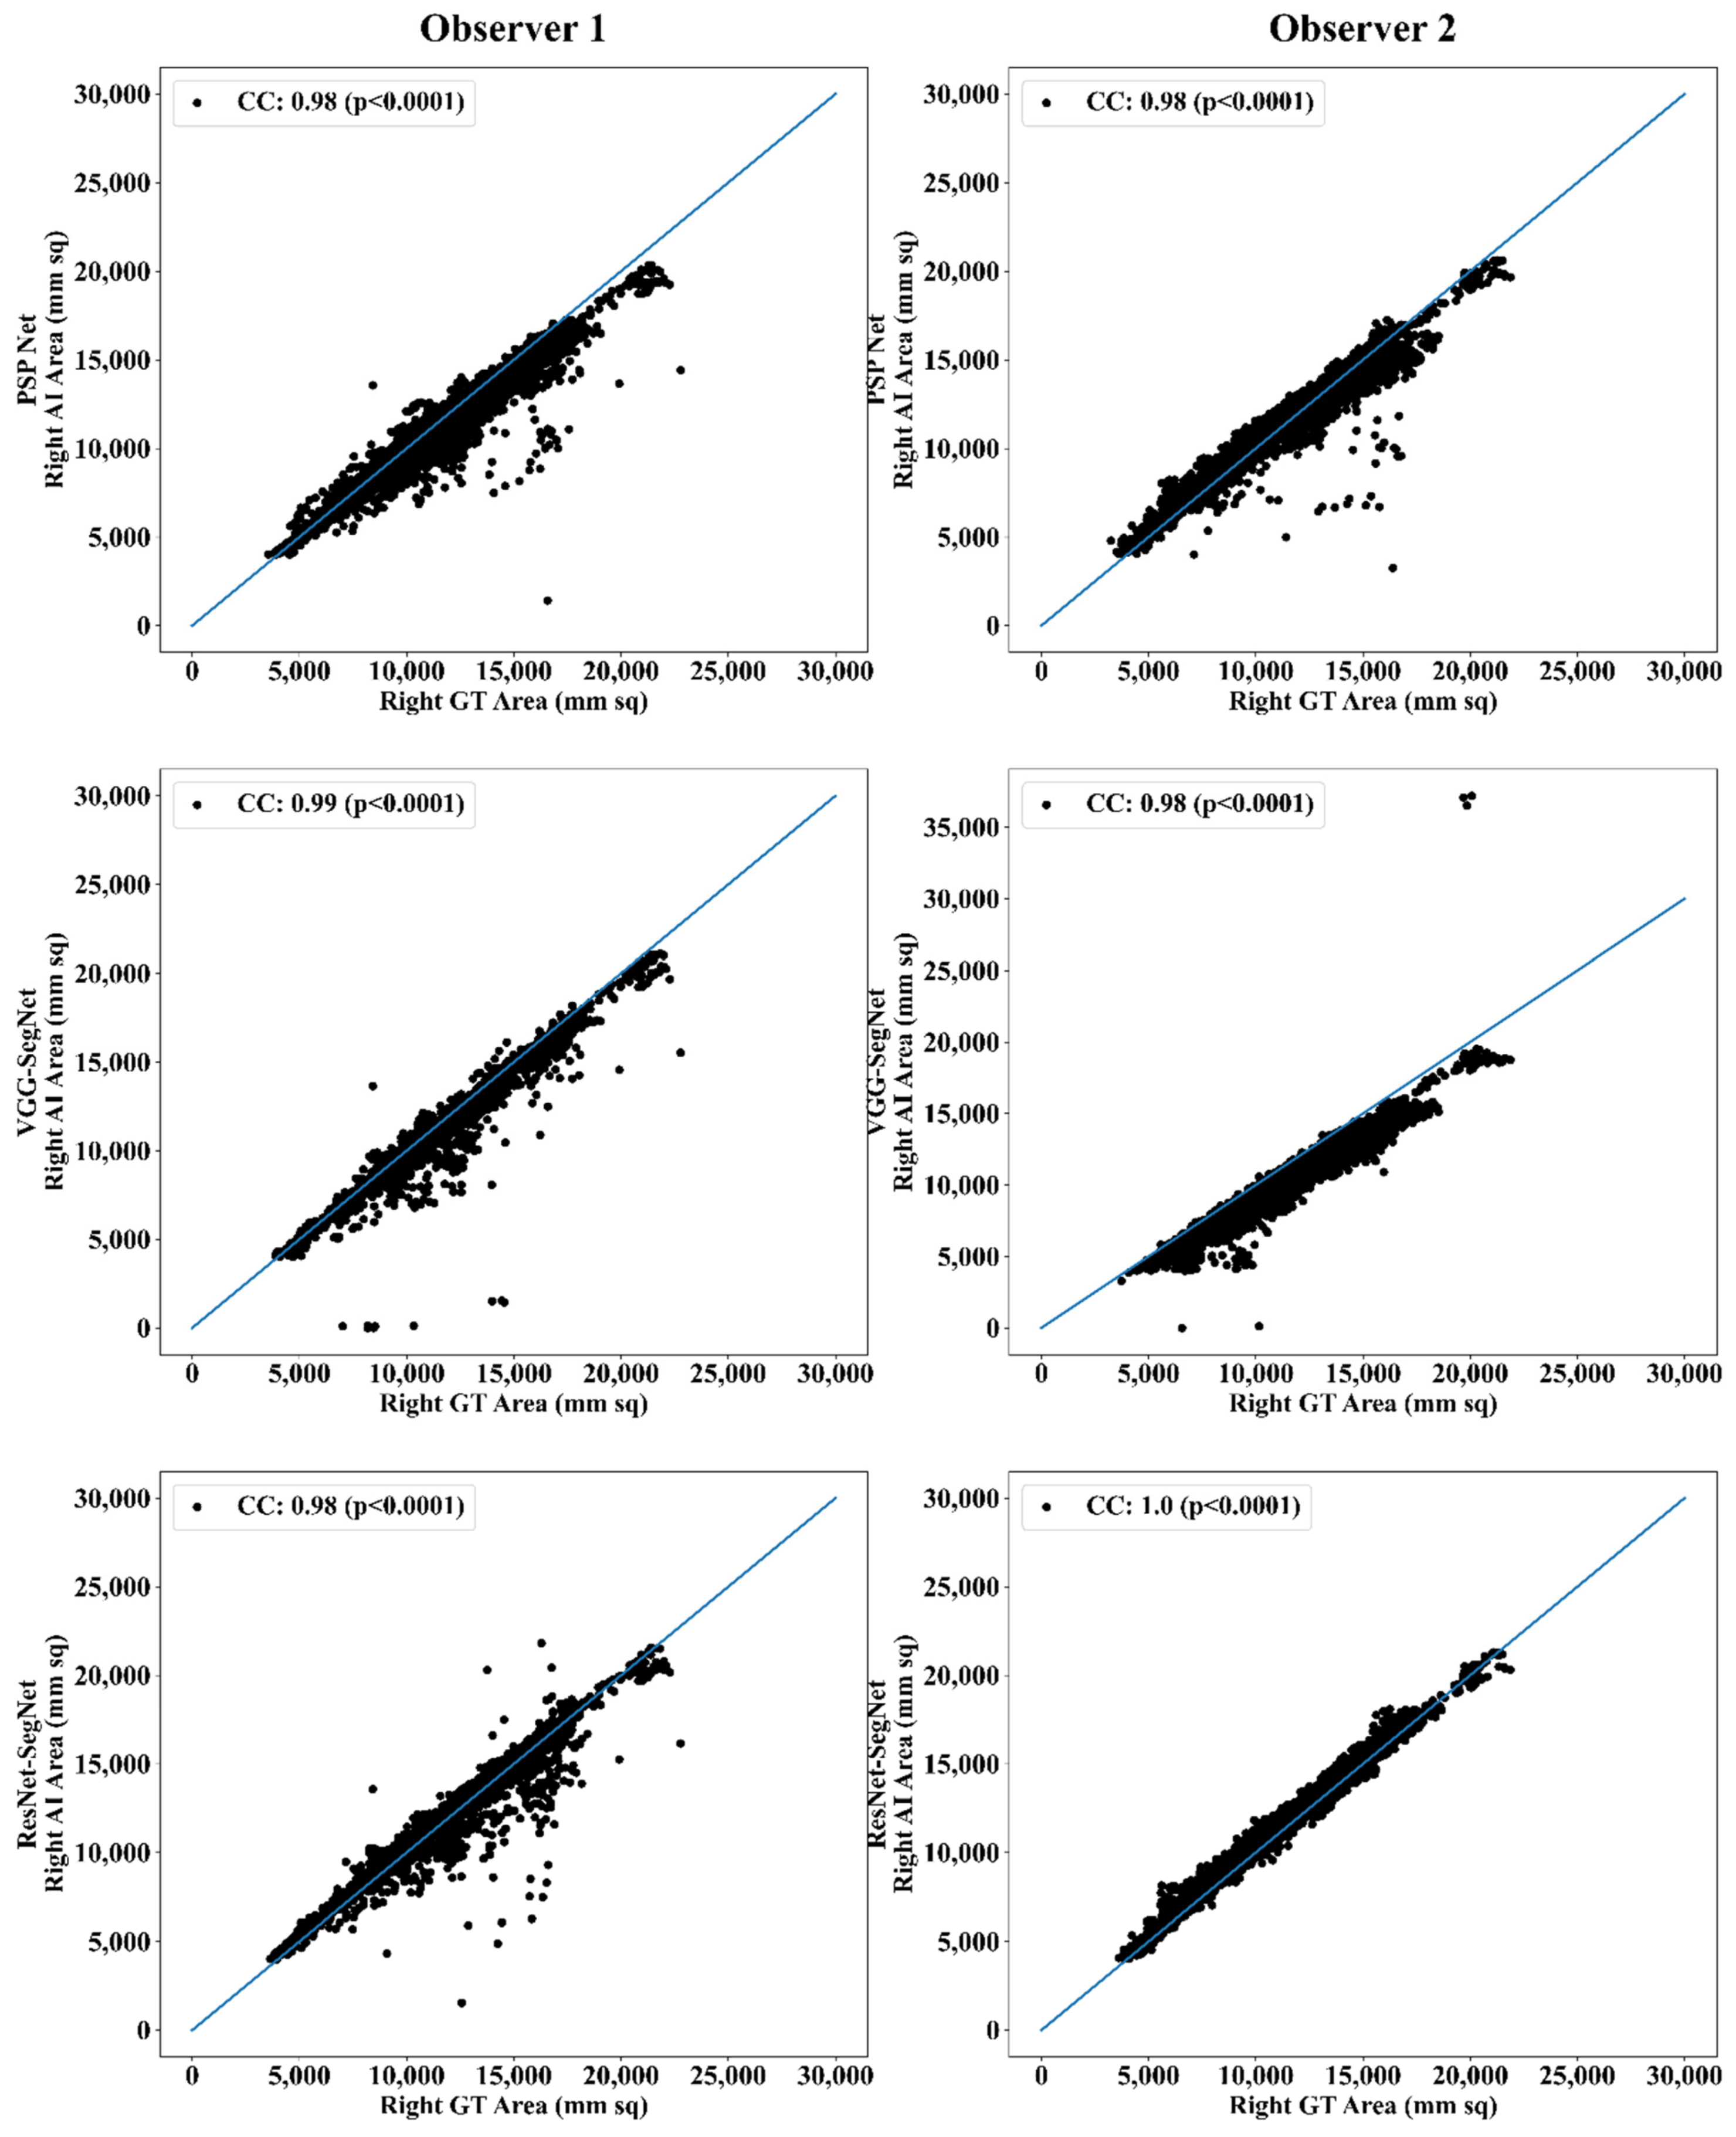

Correlation Plot for Lung Area Error

| PSP Net | VGG-SegNet | ResNet-SegNet | |||||||

|---|---|---|---|---|---|---|---|---|---|

| Left | Right | Mean | Left | Right | Mean | Left | Right | Mean | |

| Observer 1 | 0.98 | 0.98 | 0.98 | 0.98 | 0.99 | 0.99 | 0.98 | 0.98 | 0.98 |

| Observer 2 | 0.98 | 0.98 | 0.98 | 0.98 | 0.98 | 0.98 | 1.00 | 1.00 | 1.00 |

| % Difference | 0.00 | 0.00 | 0.00 | 0.00 | 1.01 | 0.51 | 2.04 | 2.04 | 2.04 |